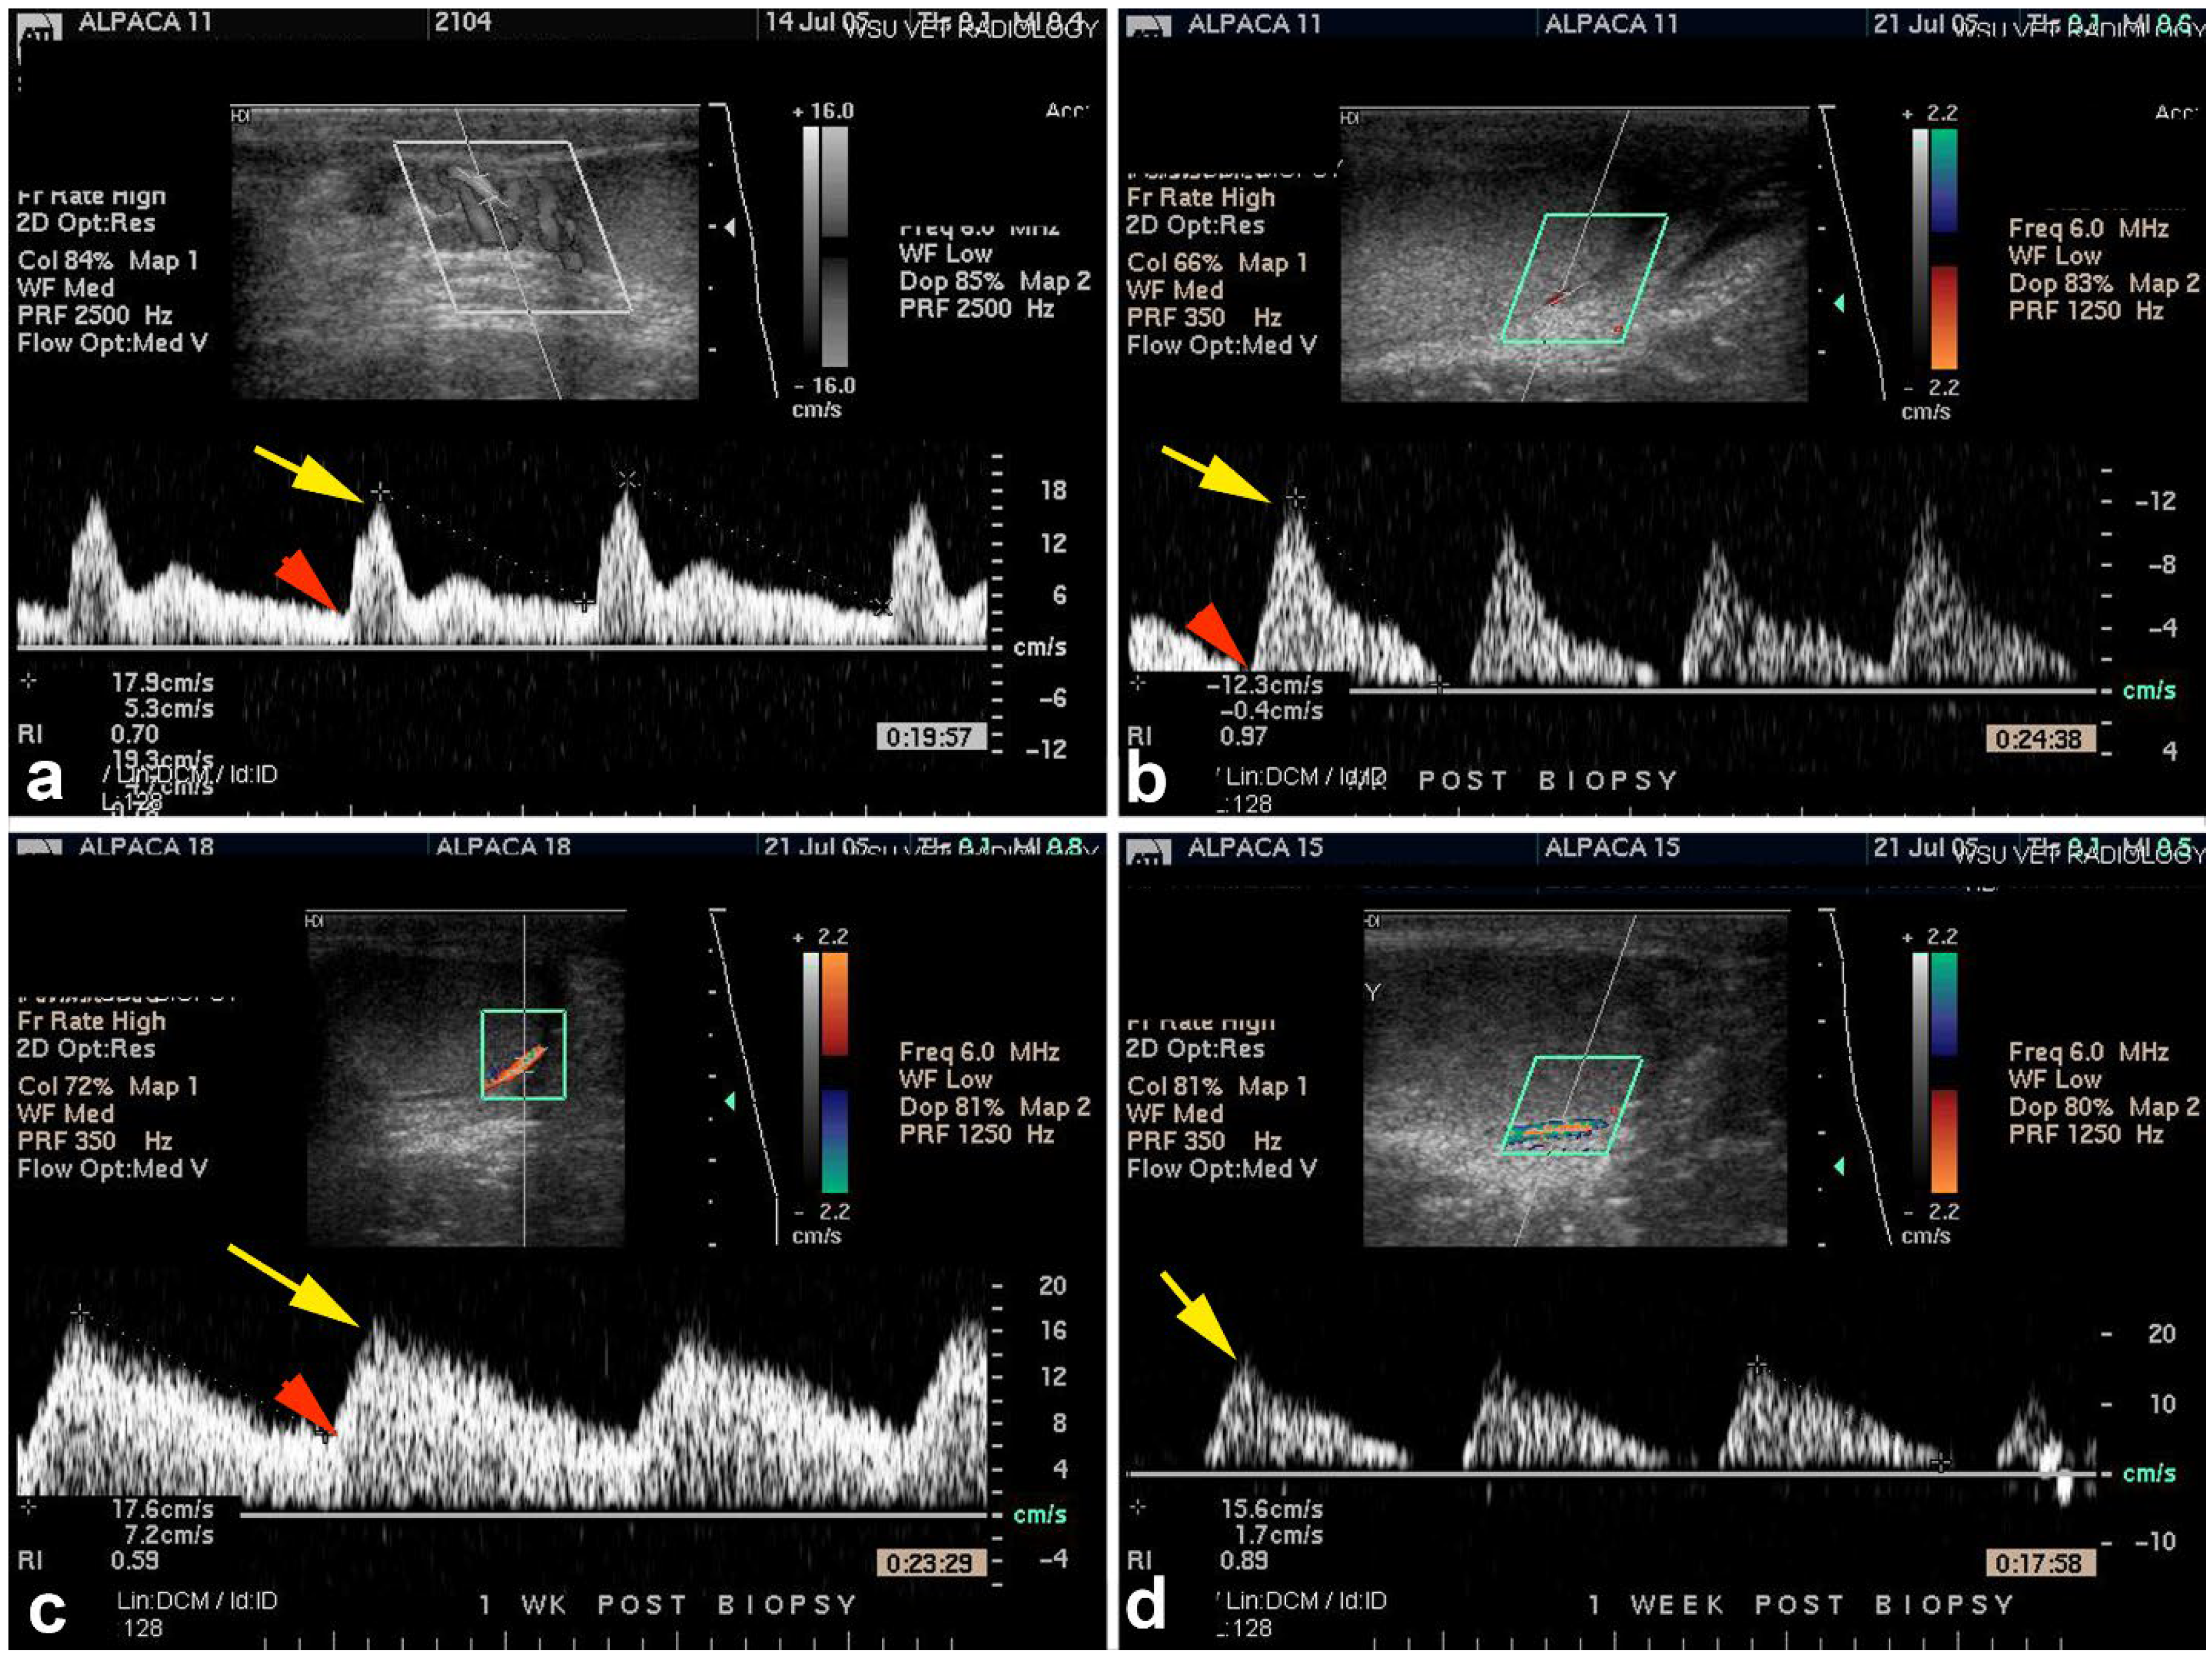

- Kutzler, M.; Tyson, R.; Grimes, M. Determination of Testicular Blood Flow in Camelids Using Vascular Casting and Color Pulsed-Wave Doppler Ultrasonography. Vet. Med. Int. 2011, 1, 638602. [Google Scholar] [CrossRef]

- Pérez-Durand, M.G.; Massa-Guzmán, A.; Luque-Mamani, N. Age-Related Differences in Testosterone Concentration and Its Relation to Testicular Biometrics, Hemodynamics, and Fertility in Alpacas (Vicugna pacos). Vet. Sci. 2023, 10, 429. [Google Scholar] [CrossRef]